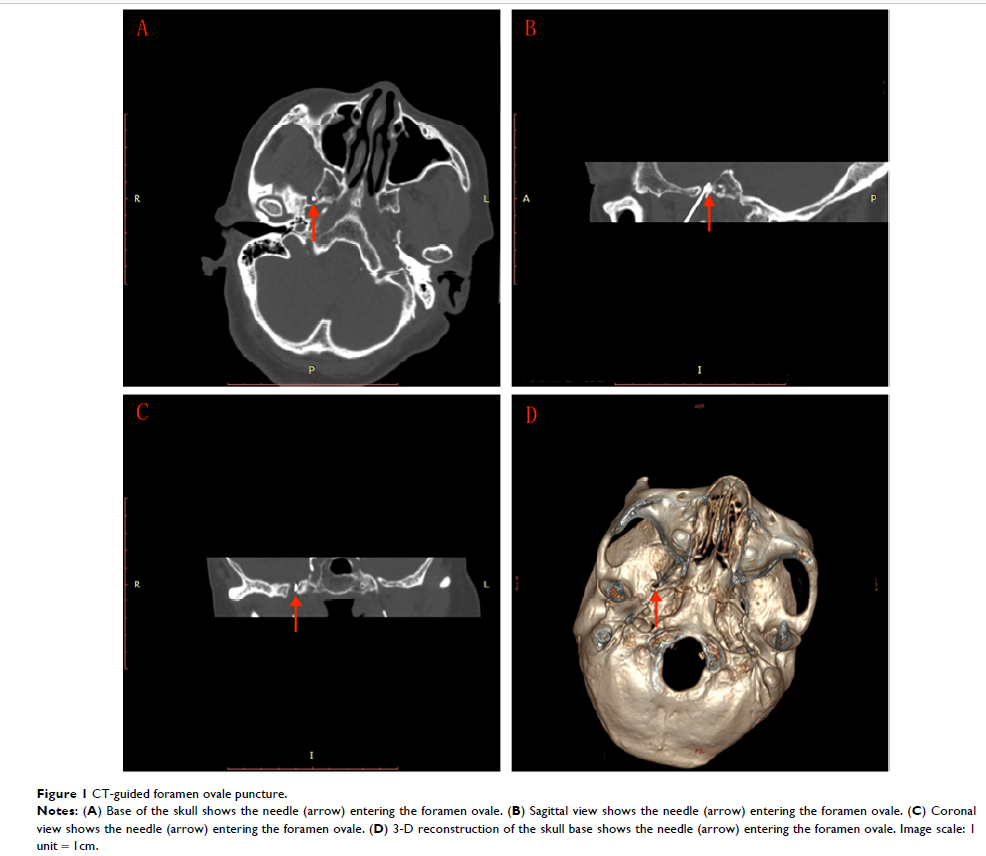

Case Series

- 作者:Meng Lan, Jia Zipu, Shen Ying, Ren Hao, Luo Fang

- 期刊:Journal of Pain Research